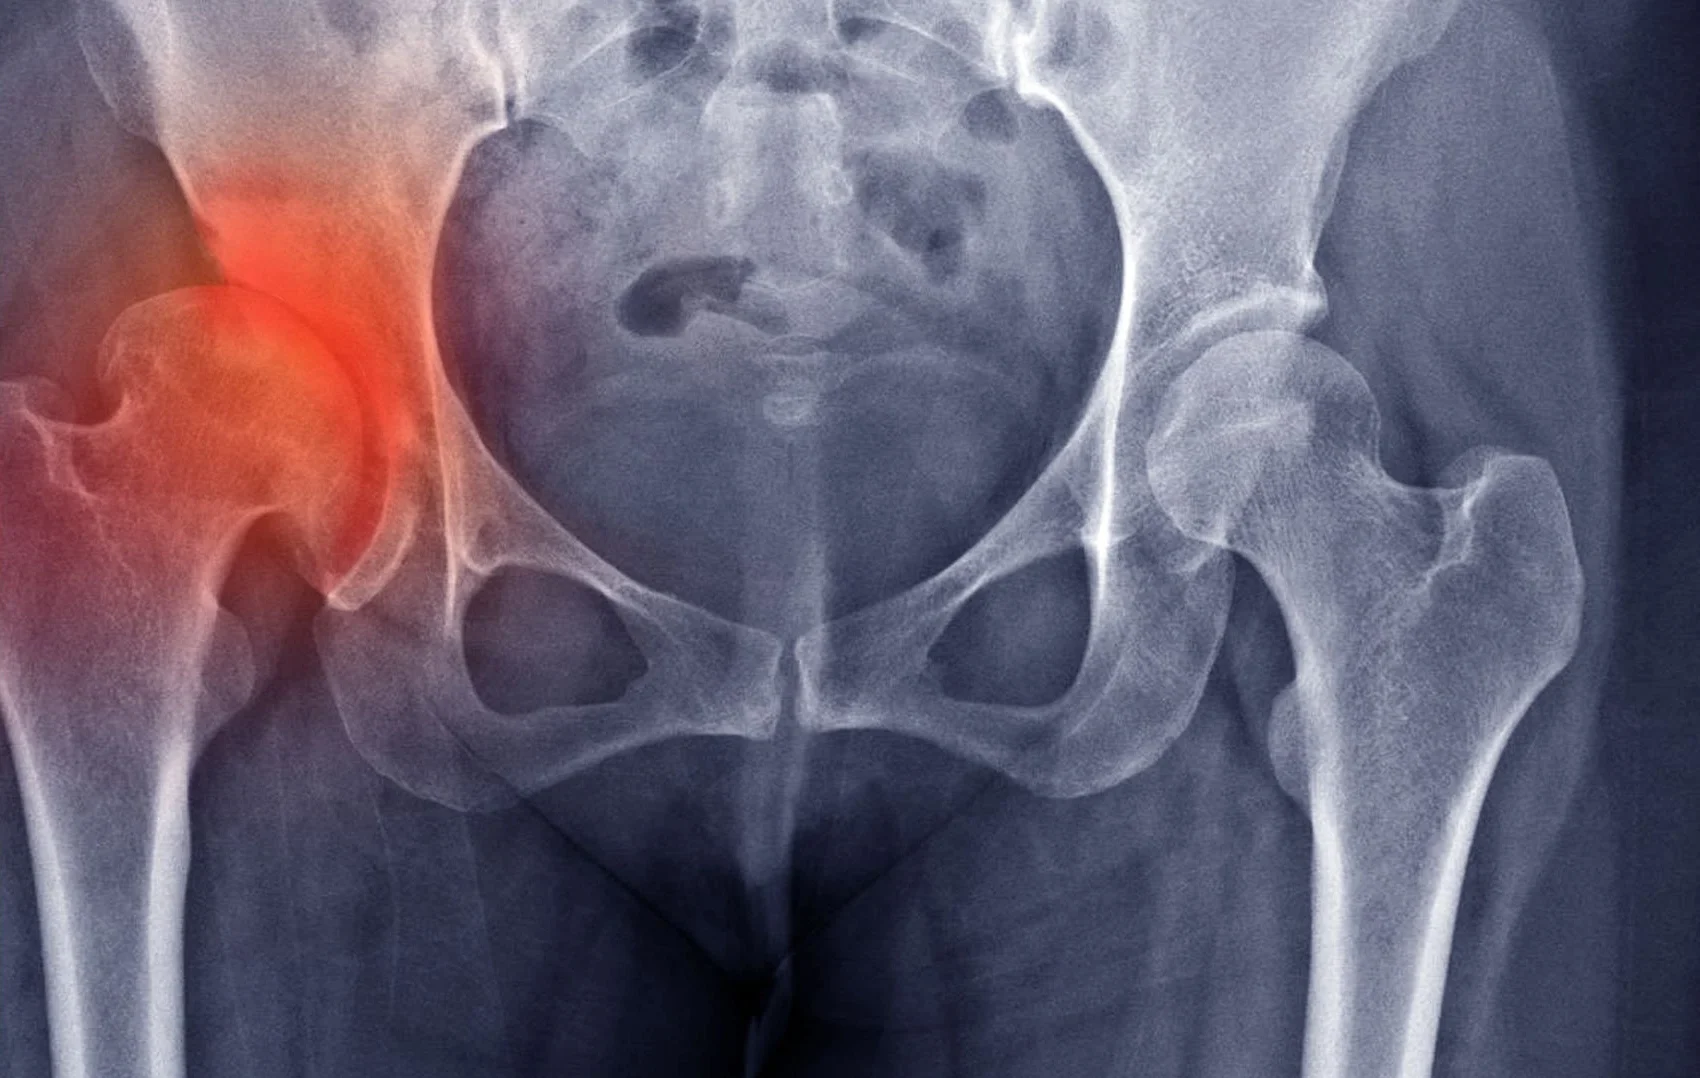

الفحوصات التصويرية

يوجد أكثر من نوع بالنسبة للفحوصات التصويرية والتي تتمثل في:

- الأشعة السينية من أجل رؤية عظام الفخذ وموقعها بالنسبة للحوض.

- الموجات فوق صوتية وتستخدم من أجل التأكد من وجود كسر يصاحب الخلع أم لا.

- الرنين المغناطيسي ويتم اللجوء إلى هذه الأشعة من أجل رؤية الأنسجة المحيطة بالمفصل ومعرفة الأضرار المحتملة من هذا الخلع على المفصل والعظام المحيطة به أيضًا.